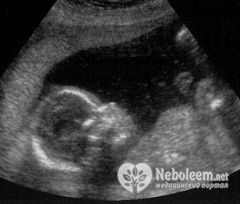

На этом сроке некоторые первородящие женщины впервые могут почувствовать шевеления плода, а те, у кого роды уже не первые, ощущают точки и удары изнутри уже на протяжении нескольких недель. Хорошо видны активные движения плода в 19 недель беременности на УЗИ.

В 19 недель беременности на УЗИ можно точно определить, мальчик или девочка находятся в полости матки.